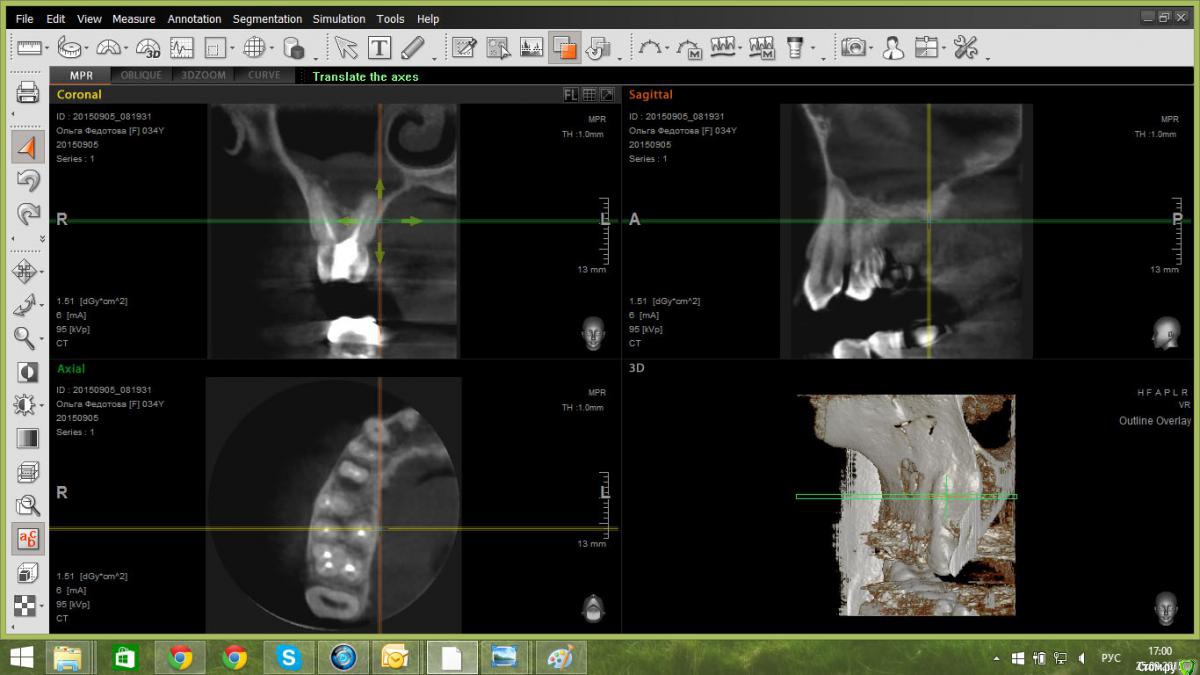

paciente Опубликовано 16 ноября, 2015 Автор Поделиться Опубликовано 16 ноября, 2015 Здравствуйте! Решила поднять тему. Хирург рекомендовал переделать КТ, т. к. предыдущее было плохого качества. По новому КТ перфорации в пазуху нет. Рекомендуют удалить пятый зуб и вычистить кисту. Но разошлись мнения врачей по поводу четвертого и шестого зубов: перелечить их перед удалением пятого зуба и кисты (но есть большой риск воспаления) или оставить как есть и наблюдать.Записалась на удаление на пятницу, но есть сомнения: лечить-не лечить?Если не сложно, посмотрите, пожалуйста новое КТ. Здесь, на форуме, рекомендовали лечить, но возможно, новые данные КТ как-то меняют ситуацию? Огромное спасибо за ответы и прошу прощения за настырность) https://yadi.sk/d/kDztiIEIkVfAh Ссылка на комментарий

paciente Опубликовано 11 июня, 2016 Автор Поделиться Опубликовано 11 июня, 2016 Здравствуйте! Снова поднимаю тему.Начала перелечивание зубов под операцию. При перелечивании шестого зуба нашли обломок инструмента в канале, отправили к терапевту-микроскописту, вместе с ней решили попробовать консервативное лечение, до этого терапевты советовали только операцию.На данный момент перелечен четвертый зуб, пятый пока остался как есть, в шестом зубе перелечены три канала из четырех, все под временными пломбами.План доктора такой: 17-го июня постоянная пломбировка четвертого зуба, затем окончательное перелечивание шестого зуба и его постоянная пломбировка, как я поняла, одновременно, потом занимаемся пятым зубом. Смущает то, что хирурги говорили, что постоянная пломбировка делается в день операции, либо максимум за день. Подскажите, пожалуйста, правильна ли тактика врача в моем случае? Врач на мой вопрос ответила, что хирург не знает об имунном ответе и, если после временной пломбировки ничего не случилось, то и от постоянной тоже ничего не будет. Так ли это?Прикрепляю сканы свежего кт, оно сделано до перелечивания четвертого зуба под микроскопом.Спасибо большое за ответы! Ссылка на комментарий

paciente Опубликовано 11 июня, 2016 Автор Поделиться Опубликовано 11 июня, 2016 https://yadi.sk/d/vsNfYLs3sRjY9 Ссылка на комментарий